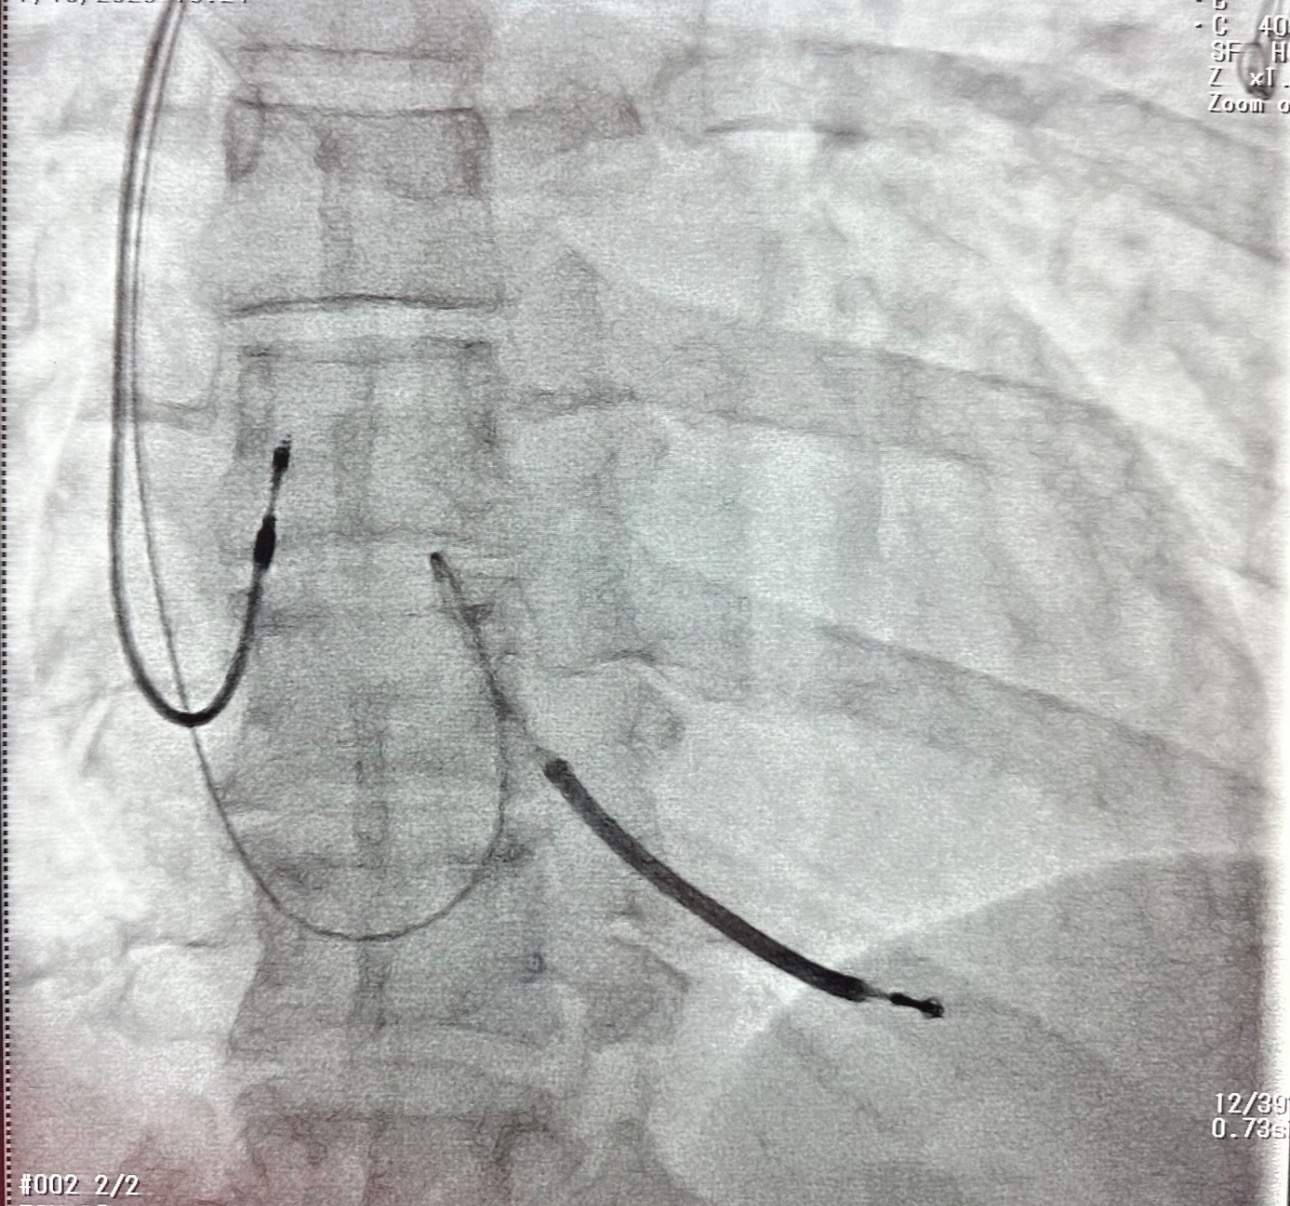

From that moment on I had 3 people in my room every hour, an alarm on my bed so I couldn’t leave it, cardiac diet, constant blood draws, pills, IV bags & vitals checked. Surgery was a must but first they had to rule everything out. I had a CT scan of my brain & heart, with & without contrast. The contrast ended up exploding in the IV & all over my hair. The vein blew & the catheter shot into my arm. An ultrasound of my heart showed scar tissue around my heart & an MRI showed no blockage which meant my heart condition is genetic. My heart was pacing between 30-40 & my blood pressure was 108

Surgery was set for July 15th. A pacemaker would be set to 70 & a defibrillator would be put in place to shock me back to life. A beta blocker would increase my survival rate & reduce hospitalization. A heart monitor next to my bed would send constant reports to my doctors so hopefully they can catch my heart going into Torsades before it actually does. Surgery went great other than me continuing to wake up during it, feeling the scalpel cutting into my chest. The physical healing will take no time at all but the mental & financial are going to be the hardest. I’m on a LOA from work & in the middle of a contentious divorce. I get zero support from the father of my children & I don’t have insurance. My kids & I would be forever grateful for any support you can give us.